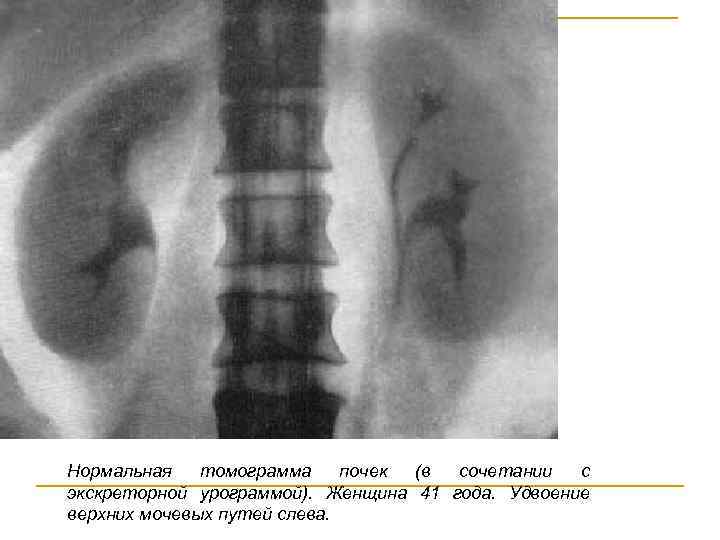

УРОТОМОГРАФИЯ Уротомография (уропланиография, уроламинография, уростратиграфия) представляет собой метод послойной рентгенографии почек, мочевых органов и органов забрюшинного пространства. Самым важным срезом при продольной томографии почек (нефротомография) является тот, который проходит через ворота почки, лоханку и почечную паренхиму. Такой срез называется основным томографическим срезом почки. Помимо основного среза, производят дополнительные с разностью расстояния 0, 5 см.

Нормальная томограмма почек (в сочетании с экскреторной урограммой). Женщина 41 года. Удвоение верхних мочевых путей слева.